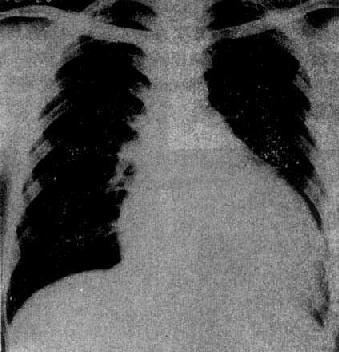

图3-2-17 慢性肺原性心脏病

心呈二尖瓣型,右心室增大,肺动脉突出,但无左心耳增大。肺动脉扩张,尤以右下肺动脉为明显,有肺门截断现象,说明有肺动脉高压。肺纹理增强,肺透明度增加,膈平而低,说明有慢性支气管炎和肺气肿